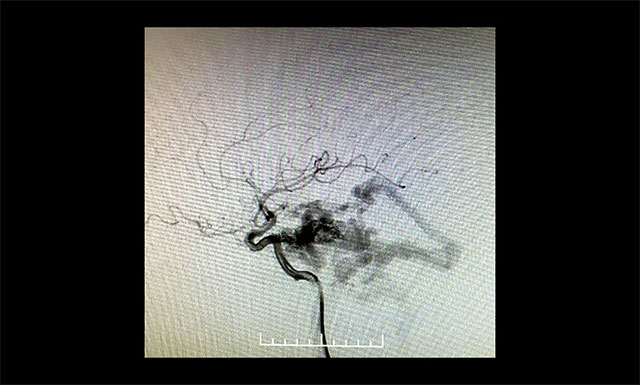

術(shù)畢左側(cè)頸內(nèi)動脈造影

▲ 術(shù)畢左側(cè)頸內(nèi)動脈造影

術(shù)畢左側(cè)頸外動脈造影

▲ 術(shù)畢左側(cè)頸外動脈造影

12月6日,患者于全麻下手術(shù)。手術(shù)順利,術(shù)中完全栓塞瘺口,重要的血管保持通暢。術(shù)后,患者牙痛癥狀消失,無新發(fā)功能缺損。